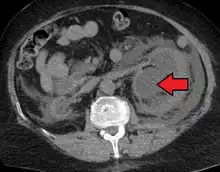

CT scan of bilateral hydronephrosis due to a bladder cancer